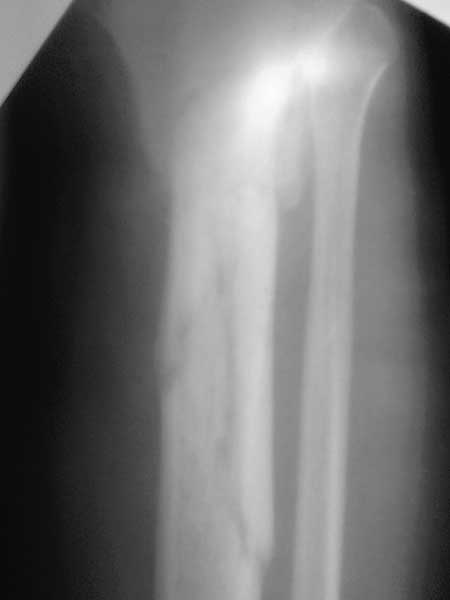

Жаль, что нет фасной проекции. Перелом на 2 уровнях, есть искривление костно-мозгового канала. Проксимальный отломок короткий. Вывод: лучше не штифтовать.

3.Перелом на 2 уровнях, есть искривление костно-мозгового канала. Проксимальный отломок короткий.